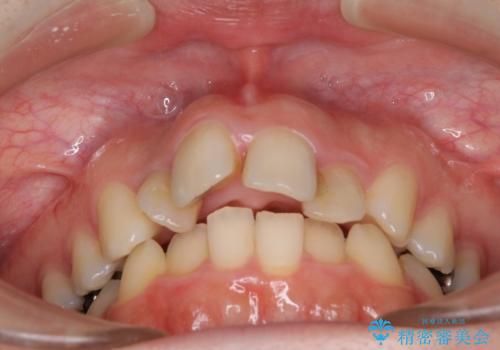

飛び出した上顎前歯とむし歯の多い歯列 目立たないハーフリンガル矯正とむし歯治療

- 上顎前歯が叢生により前方に出ている状態や、全体的なむし歯を気にして来院された患者様です。

全体的にむし歯や欠損が多く、矯正治療とは別に処置が多く必要な口腔内でした。

口元の突出感を改善するために小臼歯4本を抜歯することとしましたが、左下は大臼歯が欠損していたため、そのスペースを活用し、小臼歯を3本抜歯して治療を行うこととしました。